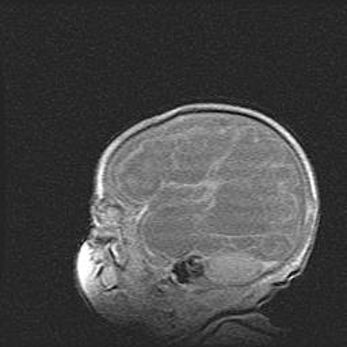

Аномалия Денди-Уокера. Признаки гипоплазии мозолистого тела.

Возраст: 5 месяцев 3 дня

Вес: 5550 г

Пол: мужской

Окружность головы: 39 см

Срок гестации: 40 недель

Аномалия Денди-Уокера – это порок развития головного мозга, для которого характерна триада симптомов: гипотрофия или аплазия червя мозжечка и/или полушарий мозжечка, расширение четвёртого желудочка с формированием ликворной кисты задней черепной ямки, гипертензионная гидроцефалия различной степени.

Гипоплазия мозолистого тела относится к дефектам внутриутробного этапа развития мозговой ткани, возникающим в процессе закладки структур головного мозга, что происходит на начальных этапах развития эмбриона.